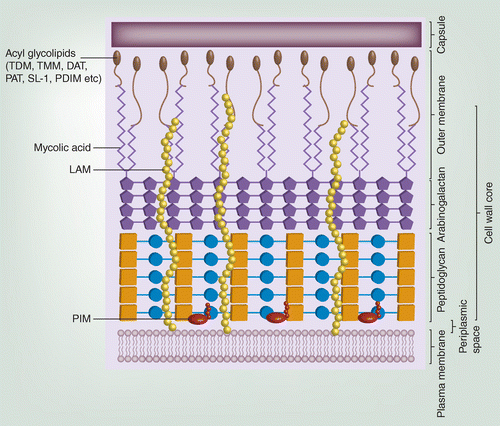

M. tuberculosis (結核病,Mtb)

-

Intracellular pathogen

- 鑽進 Macrophage

- 引發 TH1 分泌 IFN-γ,移除 Macrophage

- 太多 Macrophage 感染導致 Caseous necrosis (乾酪性壞死)

-

唯一宿主

藥

- Rifampin (RMP)

- Isoniazid (INH)

- Pyrazinamide (PZA)

- 初期

- Ethambutol (EMB)

-

疫苗: BCG (牛型分枝桿菌)